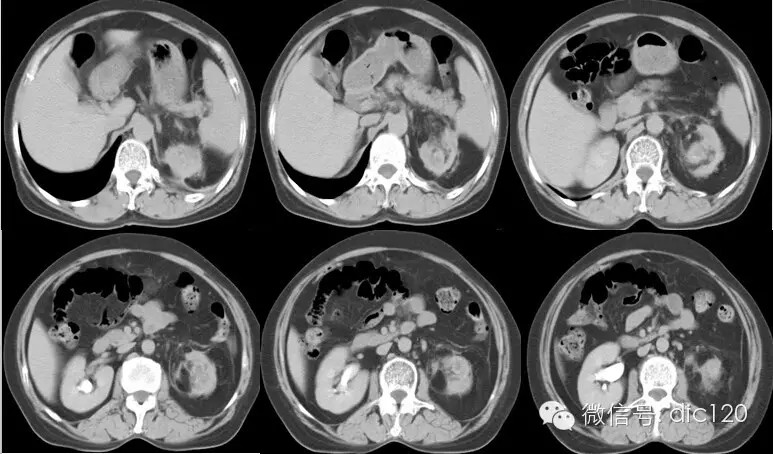

影像表现:CT平扫左肾体积变小,肾皮质变薄,肾盂扩张、壁增厚,见小点状高密度影,肾盏扩张,增强扫描病变周围组织呈环形强化,囊变区不强化,肾周模糊,筋膜增厚,临近腹膜增厚,左侧输尿管近段见结节状高密度结石影。 分析:1、中年妇女,左上腹不适;2、肾盂肾盏扩张、壁增厚,增强环形强化;3、输尿管及肾盂小结石;4、肾周筋膜增厚。 符合肾脏感染性病变,考虑黄色肉芽肿型肾盂肾炎。 |